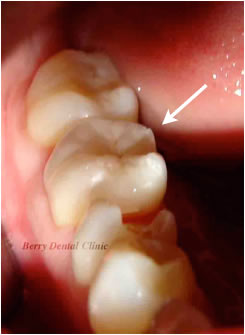

セラミックインレーをセットしました。

自然な色調で人工物とはわかりません。

噛み合わせがとても大切なので、今後も定期的に予防歯科と平行して噛み合わせのチェックも行いできるだけ長くもつようにチェックしていきます。